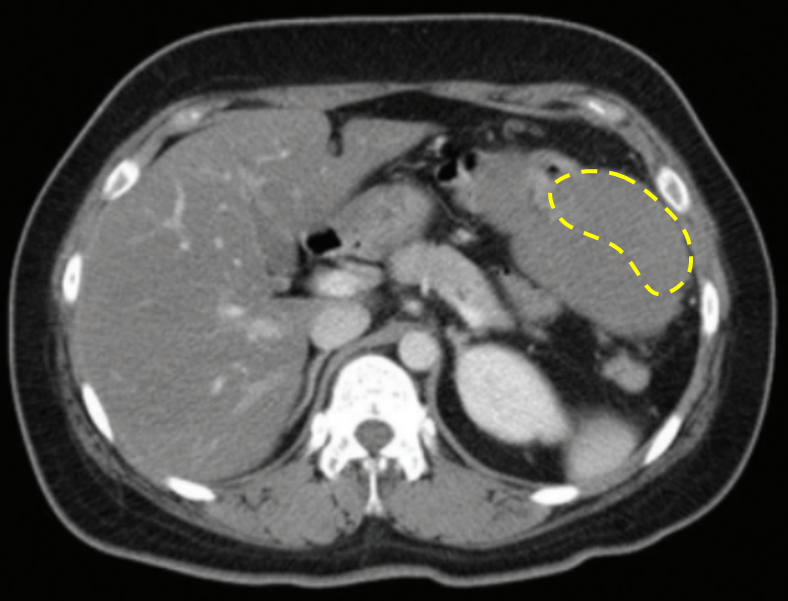

29세 여자가 1주일 전에 우연히 배에서 덩이가 만져져서 병원에 왔다. 혈압 120/80 mmHg, 맥박 72회/분, 호흡 20회/분, 체온 36.7°C이다. 왼쪽 윗배에서 주먹 크기의 단단한 덩이가 만져지고, 압통은 있으나 반동압통은 없다. 혈액검사 결과는 다음과 같다. 복부 컴퓨터단층촬영 사진 및 대장 내시경 사진이다. 진단은?

Img | Abdomen CT- large size mass, 림프절 전이(-), 주변장기침범(-) 대장내시경 - normal |

• CT만으로는 진단이 어려우나, 다른 선지 모두 배제 가능하고, 큰 size의 mass가 보이므로 위창자기질종양일 가능성이 높다.

• 지라 비대: 복부 CT에서 지라비대는 보이지 않는다.